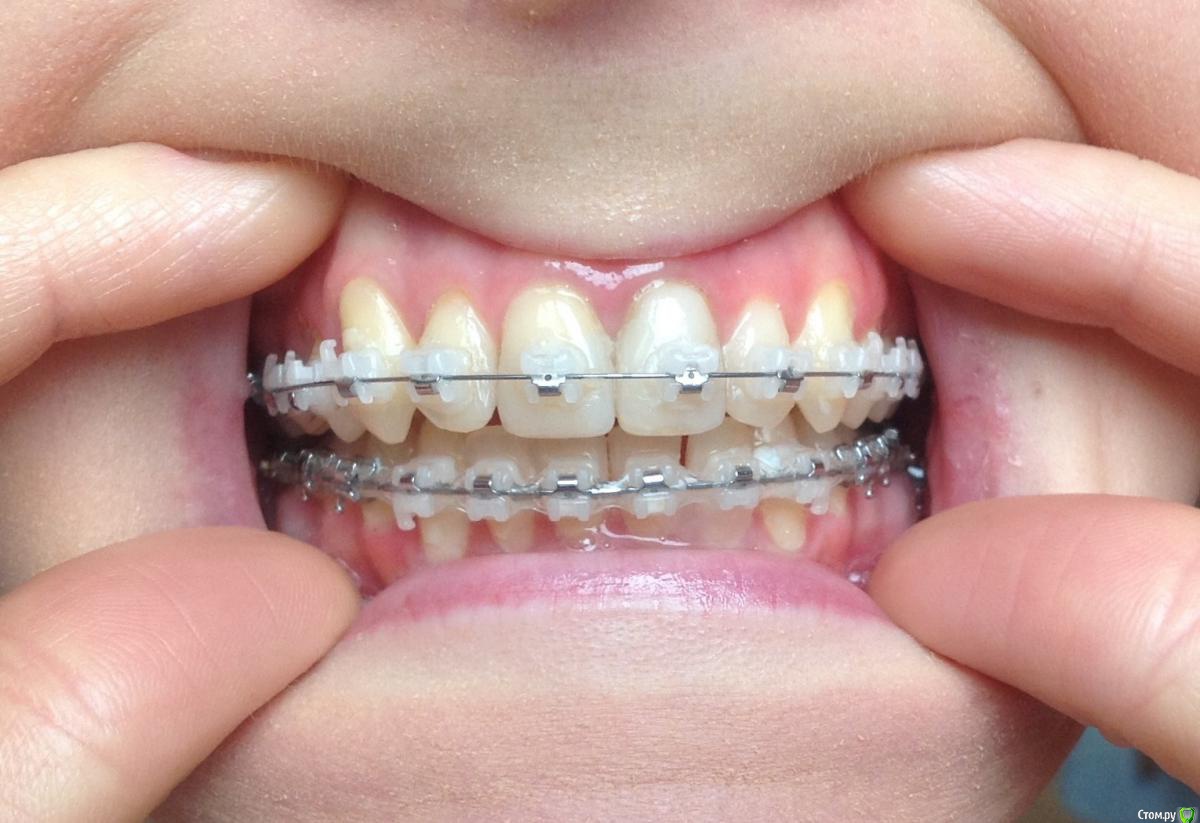

Добрый день ! Мне 29 лет. Ношу брекеты 10 мес. На данном этапе лечения сделали панорамный снимок, чтобы посмотреть ровно ли стоят корни зубов. После этого врач решил переклеить один брекет на клыке ( на снимке его видно слева ). А мне по снимку бросились в глаза , помимо этого клыка, рядом стоящий боковой резец ( он же не нравится мне как стоит и внешне) , и на нижней челюсти : 1- ый премоляр,и рядом стоящие 3 резца. Врач сказал подумать неделю и решить, хочу ли я переклеить или нет какой либо из брекетов,тк дальше они так и останутся. На её взгляд ничего переклеивать , кроме клыка, больше не нужно.

П.с. На нижн. челюсть уже поставили резинки для стягивания щелей. Я так понимаю после этого этапа уже на них брекеты не будут переклеиваться ?

Главный вопрос : Нужно ли мне переклеивать еще какие- нибудь брекеты , опускать или поднимать какой- либо из зубов, чтобы добиться большей эстетики и в дальнейшем правильного прикуса ? Или же не нужно. Заранее спасибо за внимание.